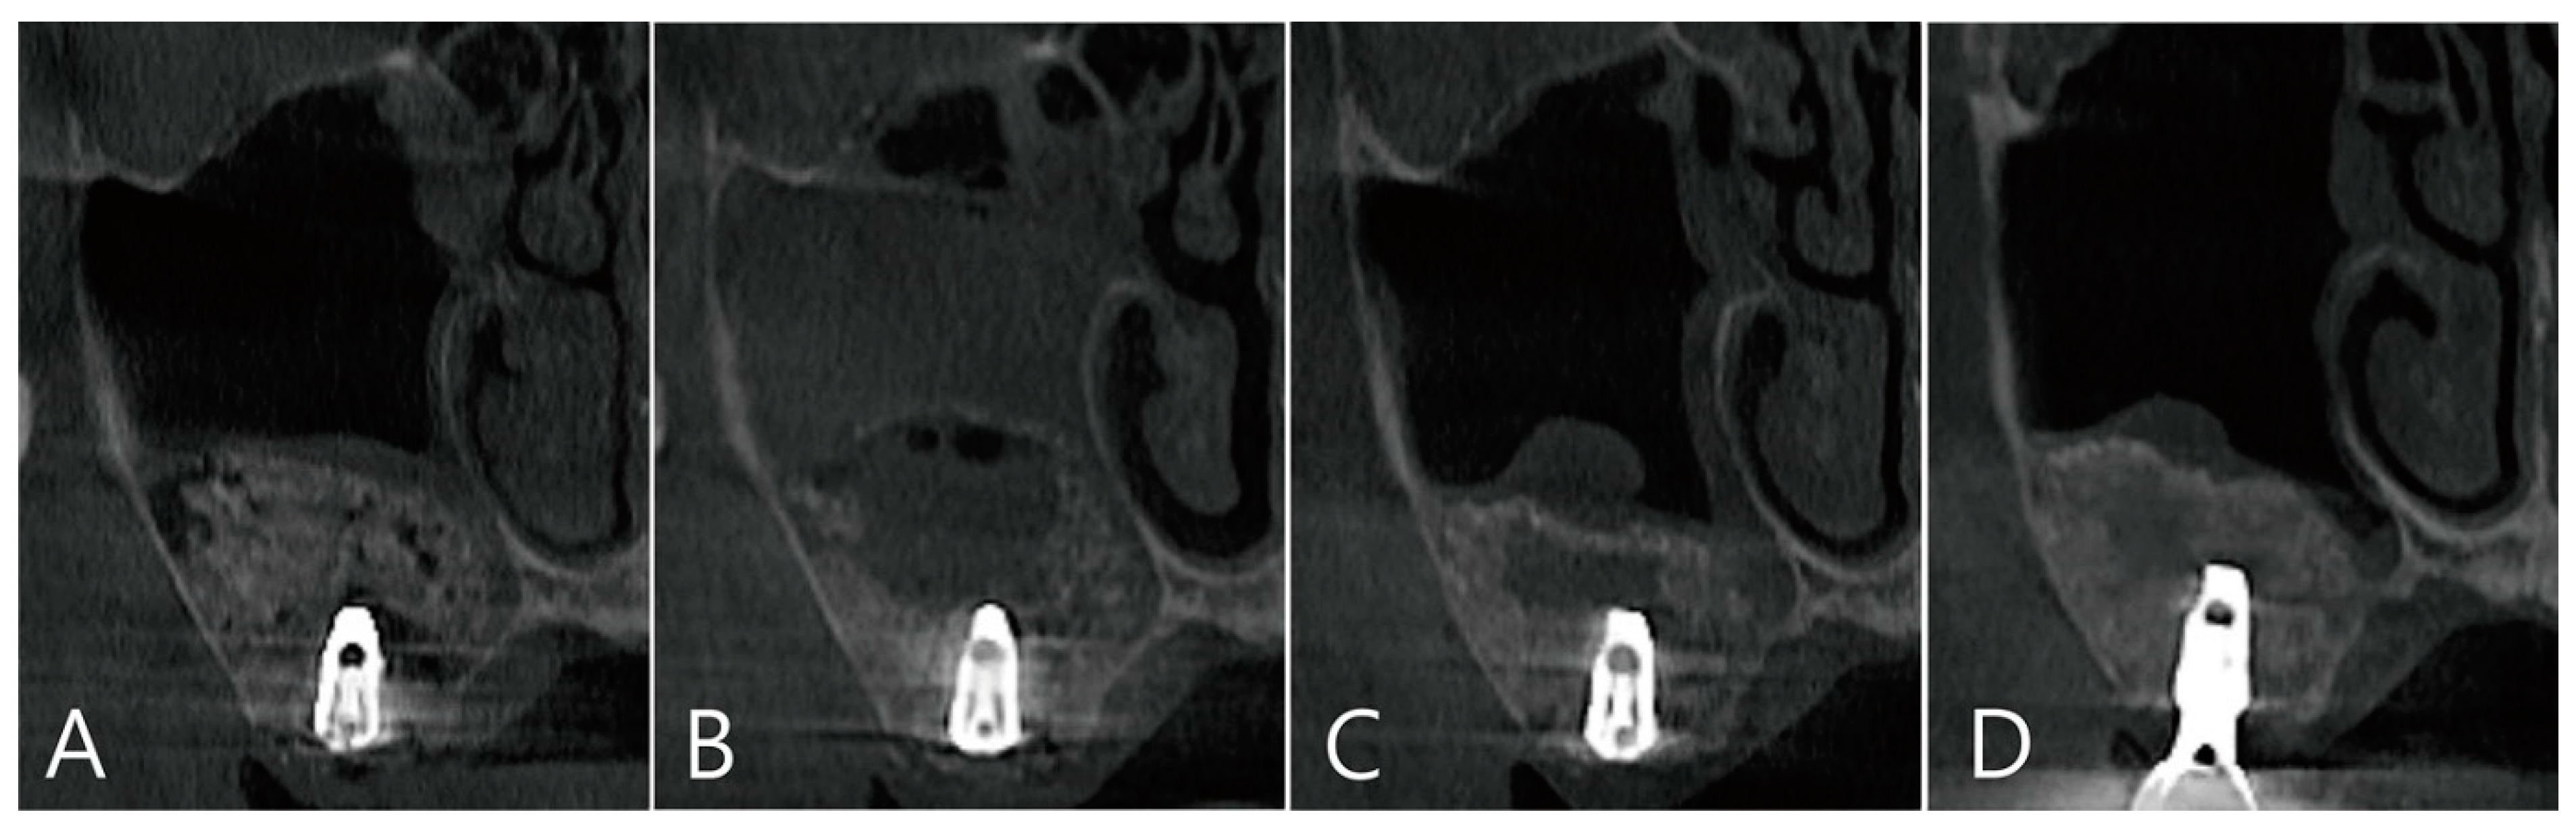

CBCT was taken immediately after MSA, one week after surgery, and before the uncovering procedure (Figure 3A–C). On the coronal image of the CBCT taken immediately after surgery, it was confirmed that MSA and implant placement were performed at the same time, and no dislocation of the bone graft particles was observed (Figure 3A). On the coronal image of the CBCT taken one week after surgery, severe grafting voids occurred on the upper part of the implant apex, and the maxillary sinus membrane was also thickened severely (Figure 3B). On the CBCT taken just before the uncovering procedure, the grafting void decreased in size, but a radiolucent image resembling SCC was observed. The thickened maxillary sinus mucosa was also reduced (Figure 3C). The grafting void was removed and a prosthesis was delivered. On the CBCT taken 6 months after the prosthesis was delivery, the radiopacity of the removed grafting void site was increased (Figure 3D).

Figure 3. (A) Coronal image of the CBCT taken immediately after surgery. There was no perforation of the maxillary sinus membrane and no leakage of the bone graft substitute; (B) coronal image of the CBCT taken one week after surgery. A severely enlarged grafting void was observed above the implant apex, and the ostium was obstructed due to severe membrane thickening; (C) coronal image of the CBCT taken 6 months after surgery. Although the grafting void was reduced in size, it appears similar to the SCC; (D) the radiopacity of the removed grafting void site was increased in the CBCT images taken 6 months after the prosthesis was delivered.